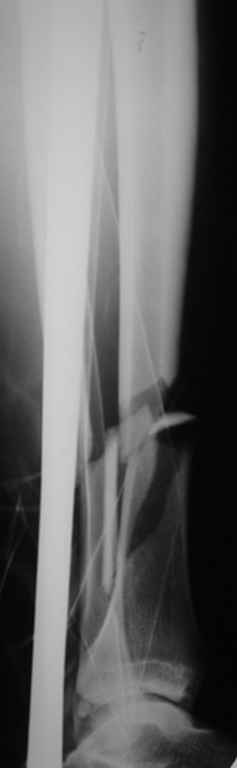

Консультировал рентгенограммы после интрамедуллярного остеосинтеза

бедра гвоздем Fixion. Пациенту объяснили, что важнее сохранить

перелом "закрытым", чем  фиксировать осколок из дополнительного

разреза. Сами собираемся оперировать голень и думаем, что без

"открытия" места перелома не обойтись.